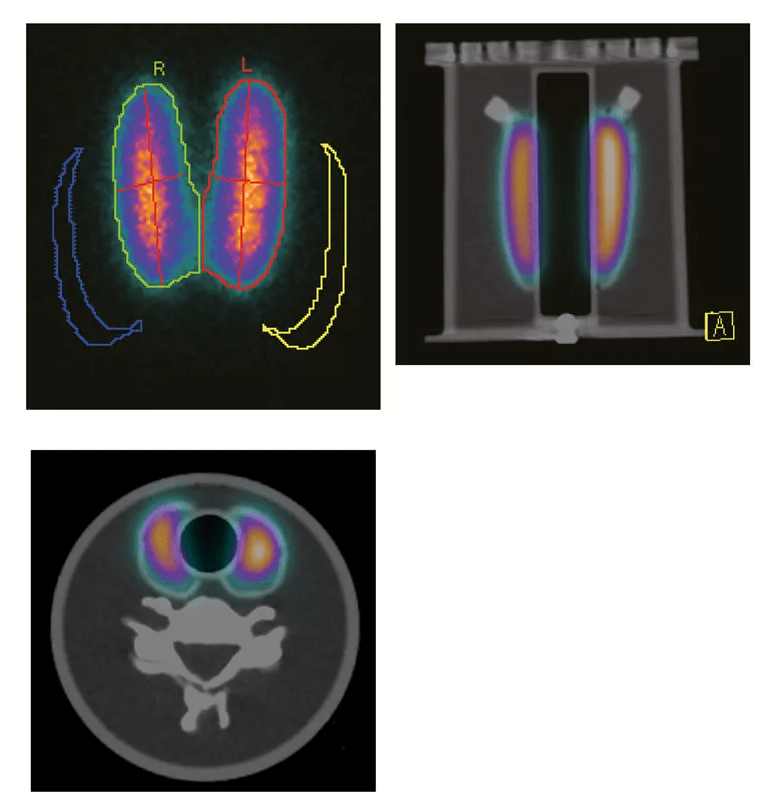

Das Phantom mit Schilddrüsen und Halswirbeln ist ein speziell entwickeltes Modell, das 5 verschiedene Schilddrüsenarten (40, 30, 21, 17, 15 ccm) für Messzwecke enthält und die Halswirbel von C3 bis C7 zur Streuung simuliert. Dieses Phantom ermöglicht die präzise Analyse der Verteilung von Radiopharmazeutika in der Schilddrüse, die für SPECT und PET sichtbar gemacht werden können. Es dient der Kalibrierung, Qualitätskontrolle und Messung von Bildgebungssystemen, um eine exakte Strahlenverteilung zu gewährleisten.

SPECT- und PET-Bildgebung: Testen und Kalibrieren von SPECT- und PET-Scannern für präzise Bildgebung.

Messung von Radiopharmazeutika: Überprüfung der Radiopharmazeutikaverteilung und Streuung in den Schilddrüsen.

Qualitätskontrolle: Regelmäßige Tests zur Verifizierung der Genauigkeit und Leistung von Bildgebungssystemen.

Forschung und Entwicklung: Anwendung in der Forschung zur Untersuchung der Strahlenverteilung und -streuung in Schilddrüse und Halswirbeln.

Das Phantom simuliert realistisch die Verteilung von Radiopharmazeutika und unterstützt die Optimierung der Bildqualität bei SPECT und PET.